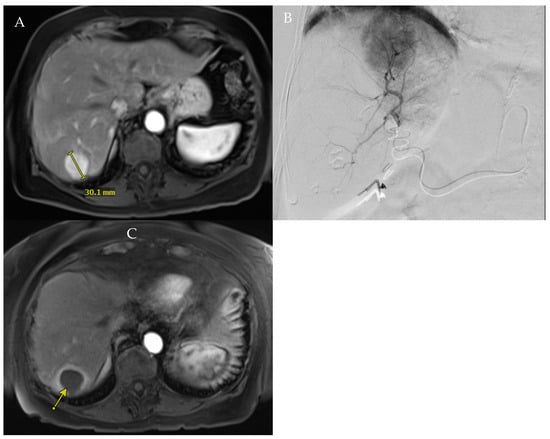

Figure 1. (A). Baseline MRI showing hyper-enhanced 3 cm tumor in segment 7. (B). Angiography of the segment 7 branch of the posterior right hepatic artery confirmed tumor perfusion. (C). Patient underwent RADSEG, with 1-month follow-up showing complete response of treated tumor (arrow).